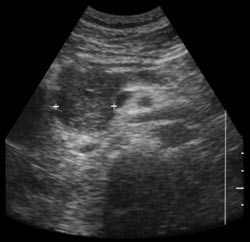

| Shadowing from bowel gas prevents visualization of pancreatic carcinoma (left). Following administration of SonoRx, a large hypoechoic mass is seen in the head of the pancreas (right). Images courtesy of Bracco Diagnostics. | |

The sonographer and interpreting radiologist were blinded to the CT and MRI results. The readers scored pre-and post-contrast sonograms of the pancreatic head, body, and tail visualization and diagnostic confidence on a scale of 1-5. In addition, each pancreatic segment was judged normal or abnormal with a confidence level of 1-5.

"We found that the sonographic visualization of the pancreas was improved after contrast, as was the diagnostic confidence," Lev-Toaff said. While scores rose in every category, the most dramatic improvements were seen in the pancreatic tail, where visualization increased from 2.0 to 3.8, and diagnostic confidence rose from 2.3 to 3.8. T-tests of the findings were also significant (p<.001) for the head, body, and tail, and sensitivity was greater post-contrast (100%) than pre-contrast (78%). Specificity remained unchanged at 88%.

Head and tail lesions that were missed pre-contrast were identified post-contrast in three patients. In addition, two nondiagnostic cases became diagnostic post-contrast, and lesions were identified post-contrast in two patients with indeterminate pre-contrast diagnoses, Lev-Toaff said. The study will continue until 50 patients have been examined.